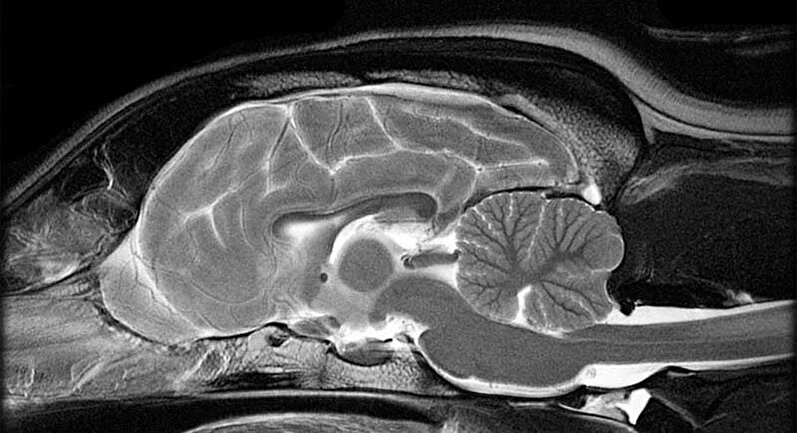

We hebben twee MRI foto's ook binnen, boven zie je gezonde hersenen ter vergelijk en onder de hersenen van Nala met de enorme tumor die alles verdrukt: